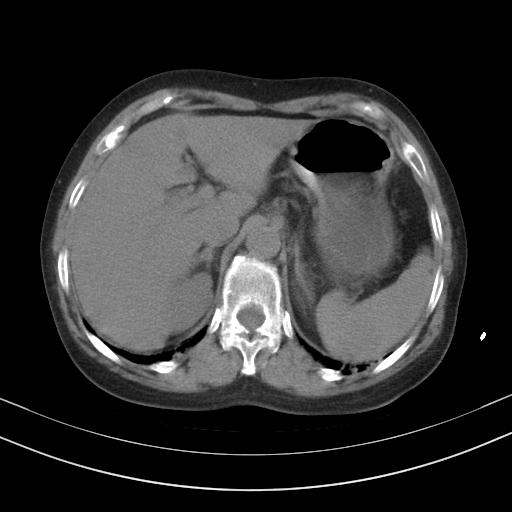

老年女性,嗜睡3天,意识模糊。轻咳,无发热。

两肺慢支炎伴感染,左侧胸腔积液。纵膈及双侧肺门淋巴结肿大建议复查。

双肺多发淡片影,毛玻璃影,,支持支气管肺炎,,建议血气找原因,,嗜睡是否肺性脑病?有没有慢支病史?

双肺炎症,建议抗炎治疗后复查,见过几个老年肺炎病例,没有发烧、咳嗽症状,直接以昏迷就诊。

1)两肺感染性病变;建议抗炎治疗后复查。2)纵隔淋巴结肿大。3)左侧胸腔积液。